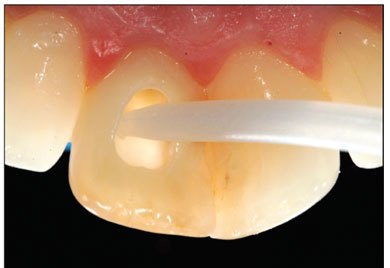

A small opening is made at the back of the front tooth to place the 'walking bleach' solution/gel. The area is sealed with a temporary restoration and the patient is left for a couple of days for the whitening to take effect. (walking bleach)

Placing gel in back of tooth

Back of tooth showing gel placement